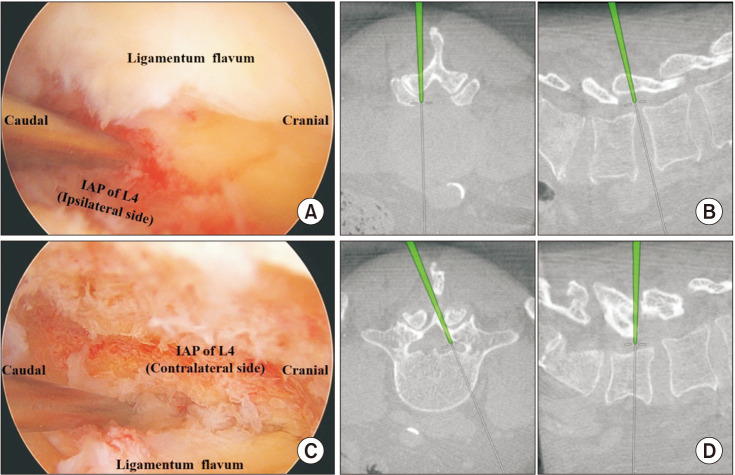

由于其微创性,需要对局部解剖有深入的了解,特别是在双门静脉内镜入路中。异常解剖、晚期退变和畸形等情况会使内窥镜腰椎减压更具挑战性。基于计算机断层扫描(CT)的手术导航系统与双门静脉内窥镜技术一起用于腰椎压缩病变。基于ct的导航系统在精度上具有明显的优势,允许在不过度骨工作的情况下进行仔细的减压,从而防止不稳定并减少错误水平手术的机会。我们描述了一般步骤,适应症,优点,手术技巧,局限性,以及避免并发症的方法。总之,使用基于ct的导航进行双门静脉内镜腰椎减压是一种有效而精确的策略,特别是在解剖结构复杂、多节段病理或明显解剖变异的病例中。

Intimate knowledge of local anatomy is required, especially in the biportal endoscopic approach due to its minimally invasive nature. Conditions such as aberrant anatomy, advanced degeneration, and deformities can make endoscopic lumbar decompression more challenging. The computed tomography (CT)-based surgical navigation system is employed with the biportal endoscopic technique to manage lumbar compressive pathologies. The CT-based navigation system offers clear advantages in precision, allowing for careful decompression without excessive bony work, thus preventing instability and reducing the chance of wrong-level surgery. We describe the general steps, indications, advantages, surgical tips, limitations, and ways to avoid complications. In conclusion, the use of CT-based navigation for biportal endoscopic lumbar decompression is an effective and precise strategy, particularly in more complex cases with challenging anatomy, multilevel pathologies, or significant anatomical variations.